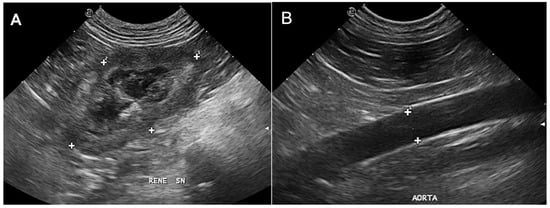

All the ultrasonographic (US) exams were performed at the Interdepartmental Center of Veterinary Radiology of the University of Napoli “Federico II” with the patient in dorsal or lateral recumbency, using the same ultrasound device (MyLab Class C Vet, Esaote, Genova, Italy). A microconvex or linear, multifrequency electronic probe (model SC3123, 3.5–10 MHz and model LA533, 3–13 MHz, respectively, Esaote, Genova, Italy) was used depending on the ultrasonographer’s preferences, which were mainly based on the best resolution achievable according to the patient’s size. All the US exams were performed by the same operator (L.M.), a professor of veterinary radiology with more than 26 years of experience in ultrasonography. The operator was unblinded regarding the patient’s clinical status and laboratory blood analysis results, if available during the exam. The KL/AoD ratio has been included in the institutional abdominal ultrasound examination protocol since May 2017 and has been assessed in all patients undergoing abdominal ultrasound using previously established methods [7]. Briefly, the KL was determined in the dorsal plane, from a subcostal or intercostal acoustic window, depending on patient conformation, and measured on a still frame acquired when the distance between the two poles was maximum and with the renal pelvis clearly delineated (Figure 1A). The aorta was assessed from the left flank, and images were acquired in a longitudinal scan just caudal to the root of the left renal artery. The measurements of the AoD were acquired at maximal luminal diameter, excluding the vessel walls, after reviewing the last frames using the cineloop function of the ultrasound device (Figure 1B).

Figure 1. Dorsal ultrasonographic image of the left kidney (A) and of the aorta (B) acquired just caudal to the origin of the renal artery. In (A), the renal length is measured at the point of maximal cranio-caudal renal length (indicated by the measurement cursors with number 1). In (B), the maximal luminal diameter is obtained after reviewing cineloop frames to account for pulsation of the aorta; measurement cursors were placed at the margin of the lumen, excluding the vessel walls.